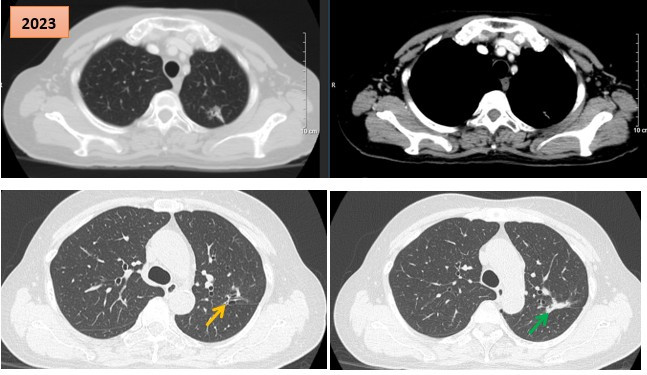

Thuốc điều trị đích giúp bệnh nhân ung thư phổi giai đoạn muộn ổn định bệnh suốt 6 năm

Friday 2026-01-30 10:04Các bác sĩ Trung tâm Y học hạt nhân và Ung bướu (Bệnh viện Bạch Mai) vừa ghi nhận một trường hợp bệnh nhân ung thư phổi giai đoạn muộn được điều trị bằng thuốc TKIs thế hệ I từ năm 2017...